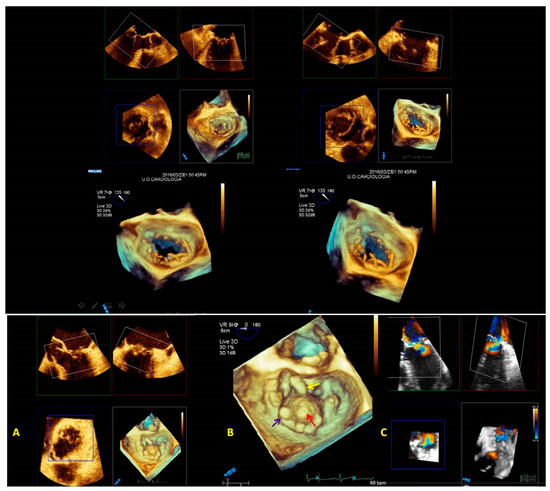

- The initial step is the guidance of the transseptal puncture. The ideal location for the puncture in most patients is the mid-fossa in the bicaval view, and the puncture site is directly visualized by the ‘tenting’ of the fossa ovalis. 3D-TEE with X-plane modality provides imaging of the entire interatrial septum (IAS). It allows the correct position and orientation of the Mullins Catheter, avoiding complications (catheter distance from aortic valve and atrial roof, Figure 20A,B).

- 2.

- The second step is the introduction of a steerable guide catheter (SGC) and advancement of the clip delivery system (CDS) into the L.A.; RT3DE with X-plane modality permits us to avoid LA free-wall injury (Figure 20C).

- 3.

- The third step is positioning the Mitraclip above the MV. RT3DE with zoom modality en face view allows determination of when the clip is adequately positioned above the middle segments of the MV and if the orientation is perpendicular to the line of coaptation (Figure 20D).

- 4.

- The fourth step is the advancement of the Mitraclip in the LV. RT3DE with zoom modality in the L.A. or LV views represent direct visualization of the MitraClip concerning the MV and the line of coaptation, lowering the overall gain to get a clear impression of the clip in the LV views (Figure 20E).

- 5.

- The fifth step is grasping the leaflets and assessing proper leaflet insertion and clip detachment.

- 6.

- The sixth and final step is assessing the procedure results. RT3DE color may be used to evaluate the residual MV regurgitation, and 3D-TEE multiplanar reconstruction may be used to assess the post-implant mitral valve area. The clip can be repositioned or withdrawn in case of severe mitral stenosis. In case of residual significant MV regurgitation, another clip can be released.